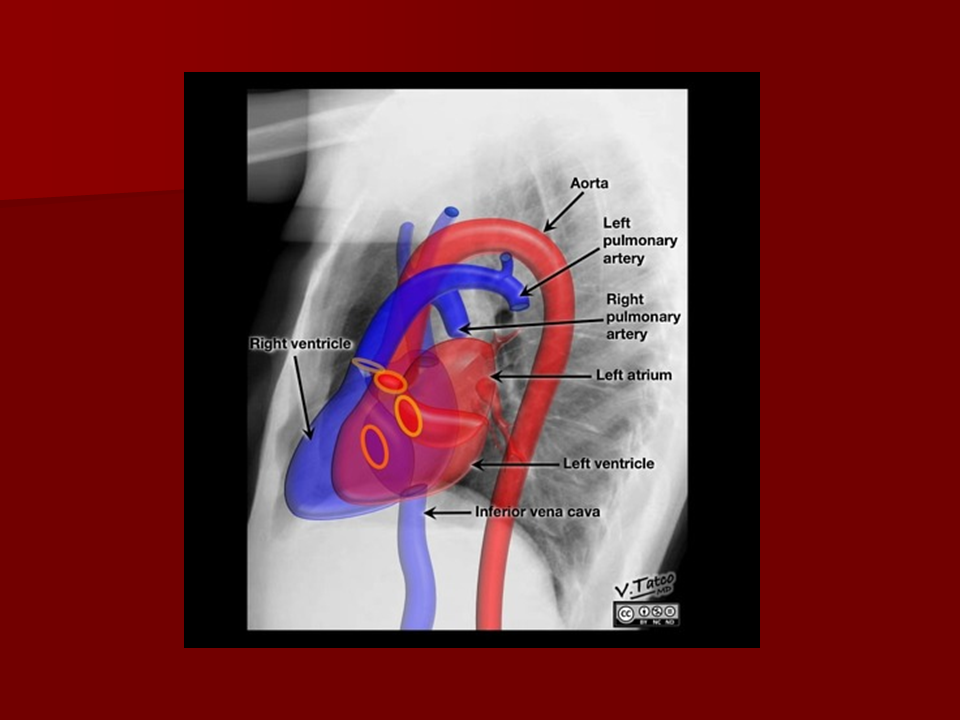

Chest X-ray anatomy